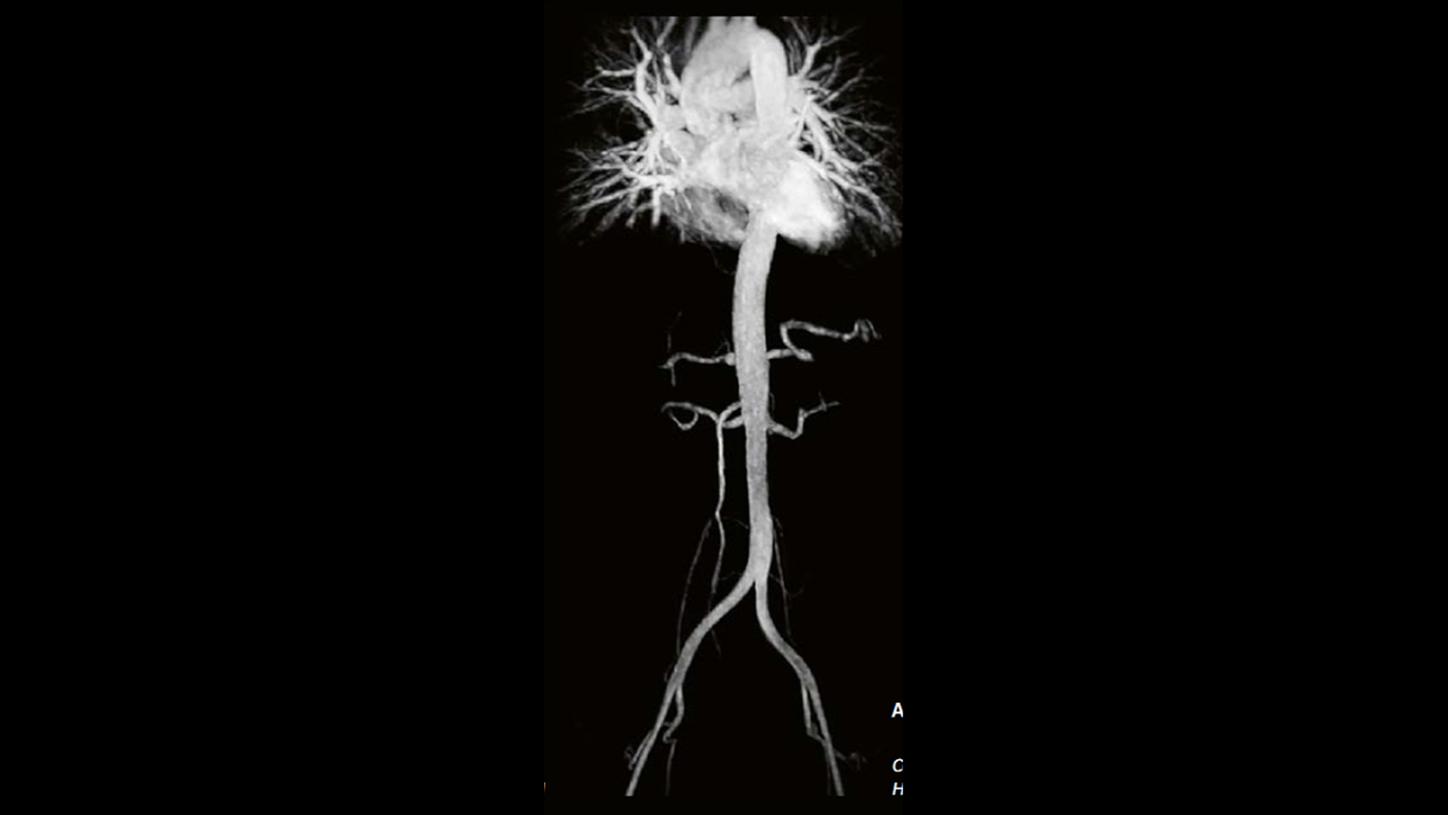

Key investigation areas for MRI are soft tissue areas like brain, abdomen, vessels, ligaments, cartilages or muscles.

Fig3: Courtesy of Radiologische Gemeinschaftspraxis, Halle/Saale, Germany

Key investigation areas for MRI are soft tissue areas like brain, abdomen, vessels, ligaments, cartilages or muscles.